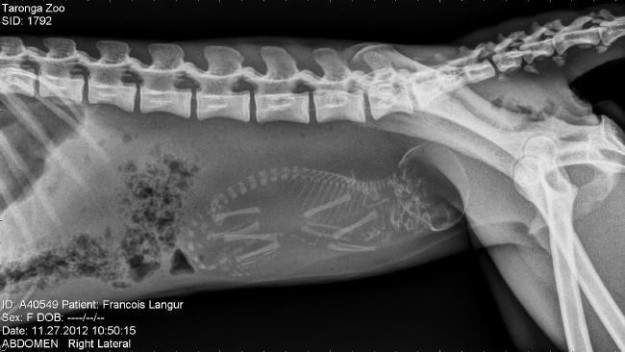

Беременная обезьяна.